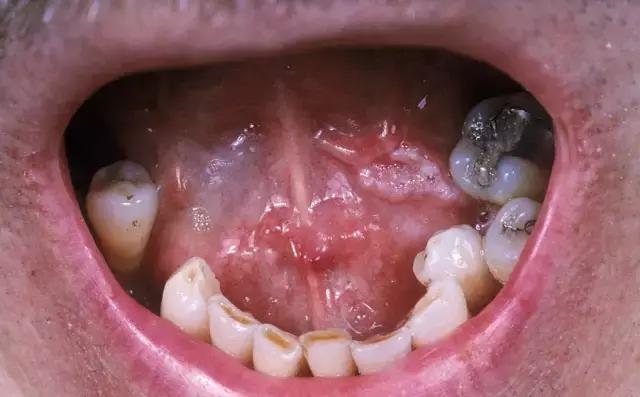

各种口腔问题引发的黏膜刺激和磨损,应尽早妥善处理